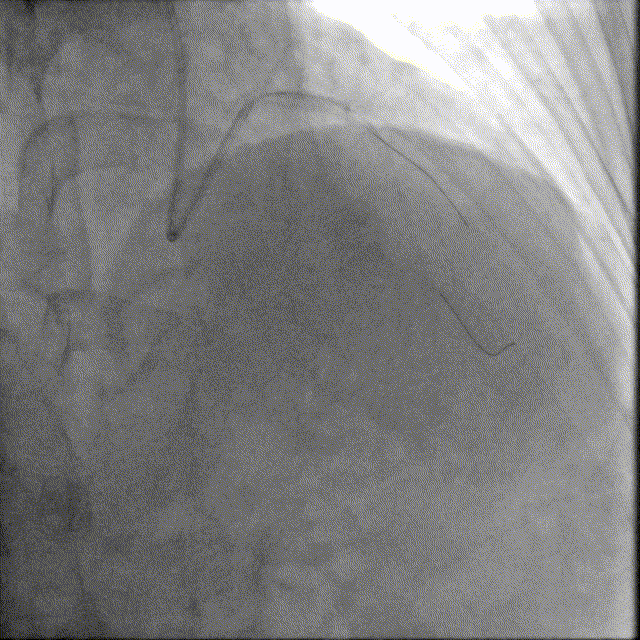

选择EBU指引导管,以2.0预扩张球囊及2.5×12mm耐高压球囊预扩前降支近段病变,可见不同程度的球囊膨胀欠佳。

冲击波导管送至左前降支,由中段至开口依次以4atm压力初始冲击扩张,6atm压力巩固扩张,共冲击扩张10秒×8个周期,可见球囊逐渐膨胀充分。此阶段在处理前降支开口时预置回旋支保护导丝。